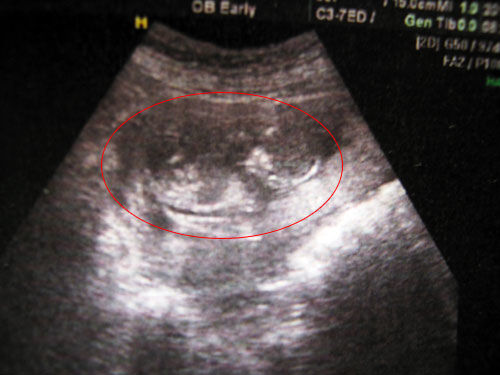

怀孕后,孕妈妈在满4个月后,即从第5个月开始母体可明显感到胎儿的活动,也就是,胎宝宝在子宫内伸手、踢腿、冲击子宫壁,孕妈妈会有明显的感受。这就是胎动!有的孕妈妈可能感受到胎动的时间比较早,有的则稍微晚一些,其实,只要胎儿发育正常,产检正常,就不要过于担心。

进入二十七周,宝妈们要学会数胎动了,每天三次,每次一个小时。如果胎动每小时大于等于三十次,那么说明宝宝在肚子里面很健康,宝妈们就放心了。如果每小时只有二十次,那么可能宝宝出现了脐带绕颈等或者其他情况。但是每小时少于十次,那么宝妈就要考虑到宝宝是否缺氧,及时去医院做检查。建议宝妈们下一个胎动计数器,动一下记录一个数,动一阵也算一个。